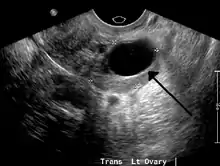

A 2 cm left ovarian cyst as seen on ultrasound

Ovarian cysts are usually diagnosed by ultrasound, CT scan, or MRI, and correlated with clinical presentation and endocrinologic tests as appropriate.[10]

Ultrasound

Follow-up imaging in women of reproductive age for incidentally discovered simple cysts on ultrasound is not needed until 5 cm, as these are usually normal ovarian follicles. Simple cysts 5 to 7 cm in premenopausal females should be followed yearly. Simple cysts larger than 7 cm require further imaging with MRI or surgical assessment. Because they are large, they cannot be reliably assessed by ultrasound alone; it can be difficult to see posterior wall soft tissue nodularity or thickened septation due to limited ultrasound beam penetrance at this size and depth. For the corpus luteum, a dominant ovulating follicle that typically appears as a cyst with circumferentially thickened walls and crenulated inner margins, follow up is not needed if the cyst is less than 3 cm in diameter. In postmenopausal patients, any simple cyst greater than 1 cm but less than 7 cm needs yearly follow-up, while those greater than 7 cm need MRI or surgical evaluation, similar to reproductive age females.[11]